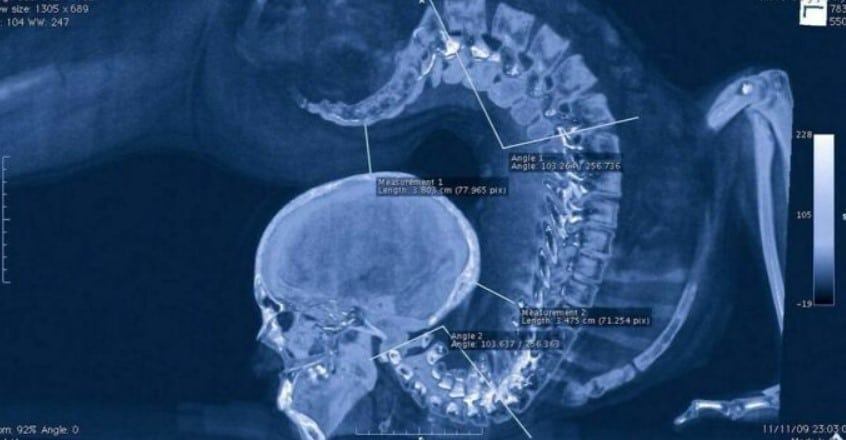

Заворот всего

Рентгеновский снимок гимнастки

Если вы покажете такой рентген неподготовленному врачу, то он может сразу отправить вас в морг, хотя на фото просто гимнастка выполняет один из спортивных элементов.